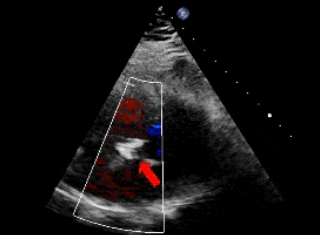

右盘面展开后,前推钢缆使其成型(左);超声下可见双盘面骑跨(右)

释放前瓣上造影,分流明显减少(左);牵拉试验,确认封堵器稳定(右)

封堵器形态良好,基本无残余分流